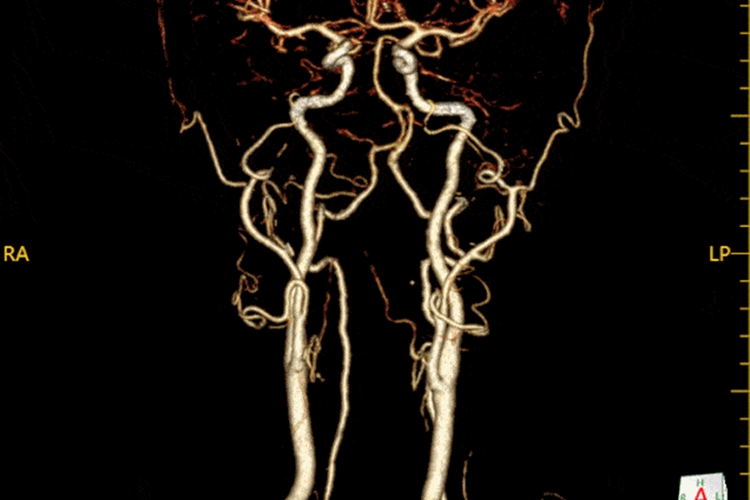

正常脑血管造影为颈内动脉经颅底入颅,先后发出眼动脉、脉络膜前动脉和后交通动脉。终支为大脑前、中动脉。正常脑动脉走形迂曲、自然,由近及远逐渐分枝、变细,管壁光滑,分布均匀。各分支走形较为恒定。CTA检查的影像图中脑动脉主干及分支明显加强,MIP技术处理后可见类似正常脑血管造影的动脉期表现。

通过观察颅脑血管CTA原始图像及血管重建图,明确是否存在大血管闭塞。通常将内径在2毫米及以上的血管划分为大血管。除了快速明确血管闭塞位置,颅脑血管CTA影像图还可以快速确定血管是否存在狭窄、钙化斑块以及弓上血管的入颅途径是否迂曲,为血管内治疗选择适合的材料和技术方案提供参照。